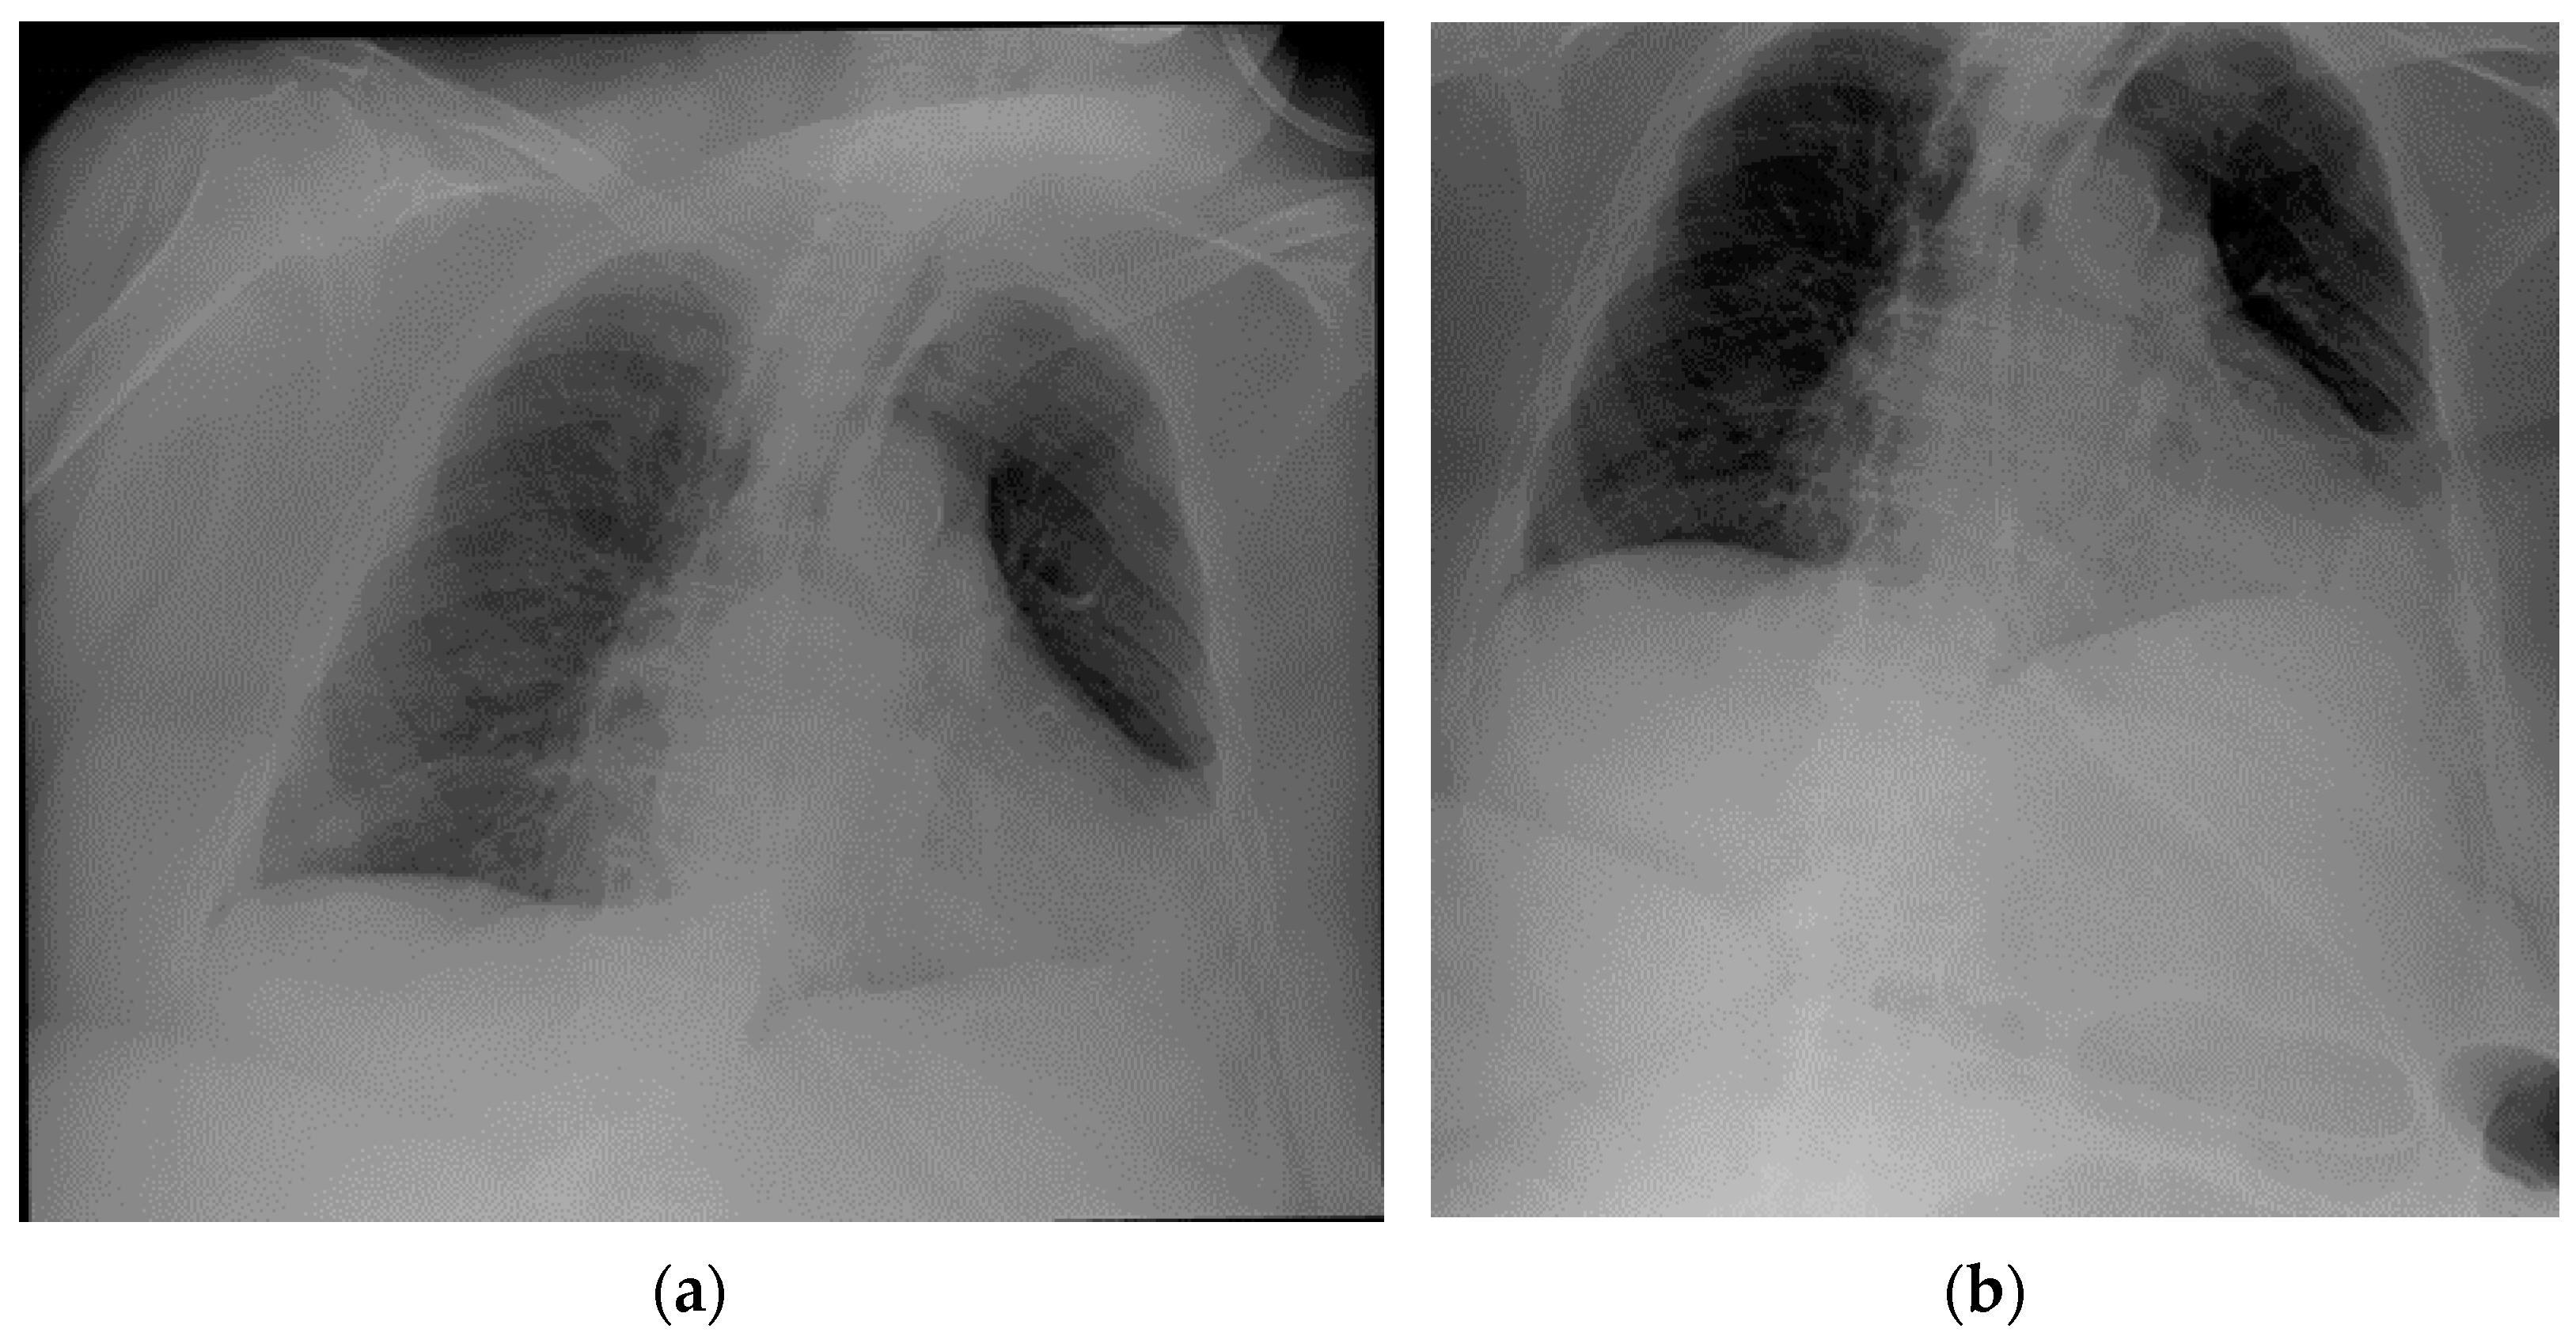

Images of a misplaced NG tube, whose tip reaches the pre-pyloric region after looping at the greater curvature of the stomach. Note that such a misposition was not visible in the regular chest projection (a), making an extended view on the upper abdomen therefore necessary (b).